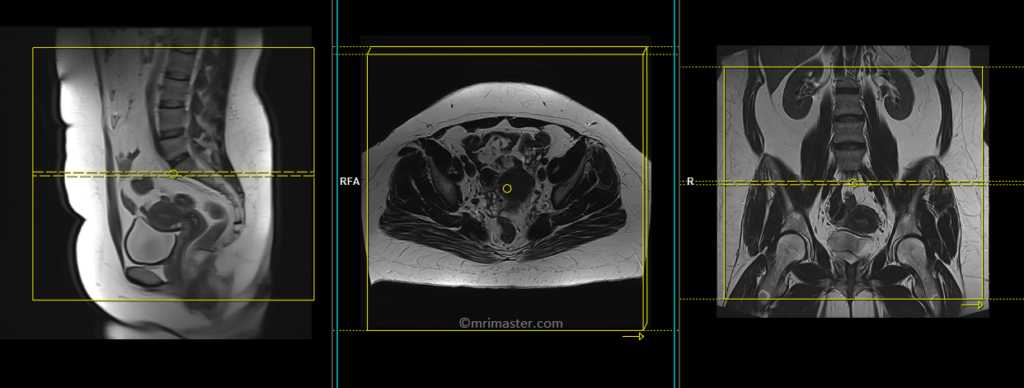

T2 tse axial 6 mm largeFOV

Plan the large field of view (FOV) axial slices on the coronal plane, position the block parallel to the line along the right and left iliac crest. The positioning block should also be checked in the other two planes. An appropriate angle needs to be established in the sagittal plane, which is perpendicular to the lumbar spine. The slices must be sufficient to cover the entire lower abdomen and pelvis, ranging from the middle of the kidneys down to the symphysis pubis. The FOV should be large enough to cover the entire pelvis, typically ranging from 350mm to 400mm. Adding saturation bands on top of the axial block can help reduce artifacts caused by arterial pulsation and breathing. Large FOV scans are usually performed to evaluate the para-aortic and pre-sacral nodes.

Parameters

TR 5000-6000 | TE 100-120 | SLICE 6 MM | FLIP 130-150 | PHASE R>L | MATRIX 384X384 | FOV 350-400 | GAP 10% | NEX(AVRAGE) 2 |